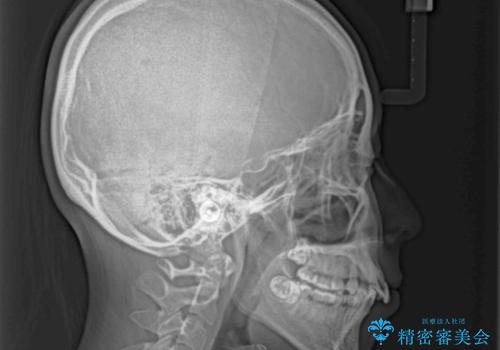

極端な出っ歯という訳ではありませんでしたが、叢生が強かったため、上下左右の第一小臼歯4本を抜歯し、少しでも口元の突出感を改善できるよう治療計画を立案しました。

下顎前歯が隠れるほどのディープバイトであり、それによる顎の負担も大きかったため、ディープバイトもしっかりと改善できるよう、表側のワイヤー装置にて矯正治療を行うこととしました。

骨格的に下顎骨が左側にシフトしていたため、上下正中の位置や左側臼歯部の咬合を理想的に仕上げることはできませんでしたが、非常に綺麗な口元を達成することができました。